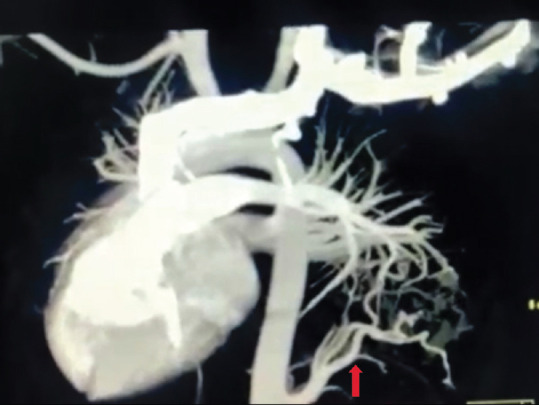

肺动脉闭塞症和囊性肺腺瘤样畸形是罕见的先天性肺囊性疾病。因此,在同一个人身上同时出现这两种疾病的情况非常罕见。肺封闭是一种无功能的肺组织肿块,其血液供应来自肺循环以外的全身血液供应。先天性囊性肺腺瘤样畸形是一种由异常支气管气室和功能性肺泡缺乏组成的肿块。本病例报告了一名 9 岁女孩的病例,她在过去 15 天里出现间歇性发热、左侧胸痛和咳嗽,并且自孩提时代起就反复咳嗽,这提示她患有混合性肺动脉栓塞、先天性肺囊样腺瘤畸形和右心室突出症。

Pulmonary sequestration and cystic pulmonary adenomatoid malformation are rare congenital cystic disorders of the lungs. The presence of both the diseases in the same individual is therefore very uncommon. Pulmonary sequestration is a nonfunctional pulmonary tissue mass that derives its blood supply from systemic blood supply other than pulmonary circulation. Congenital cystic pulmonary adenomatoid malformation represents a mass consisting of abnormal bronchiolar air spaces and a deficiency of functional alveoli. This is the case report of a 9-year-old girl with intermittent fever, left-sided chest pain, and cough for the past 15 days along with recurrent coughs since childhood suggestive of hybrid pulmonary sequestration, congenital cystic adenomatoid malformation, and dextrocardia.